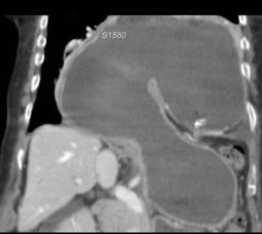

Hernie hiatale de type

I en coupe axiale TDM , fenetre mediastinale .

La poche hydro-aerique gastrique glisse alongee au

dessus hiatus oesophagien en arriere aureillete

gauche et ventricule gauche . |

Meme cas en coupe frontale (

coronale ) .Le cardia et une partie de estoma

situent au dessus le diapragme . Image du

coupe est si nette |